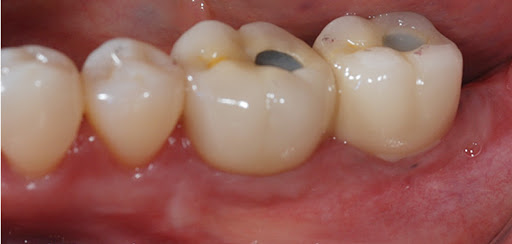

01 우수한 치아의 교합과 강도

치아의 정상적인 교합은 저작 능력을 높이며 치아의 불필요한 마찰을 줄여 치아가 갈리거나 수명이 줄어드는 것을 방지할 수 있습니다.

▶ 상악과 하악의 명확한 교합을 위해 적정한 각도로 임플란트를 식립하여 정교하고 강도 높은 보철 제작으로 실제 사용 시 불편함을 제거합니다.